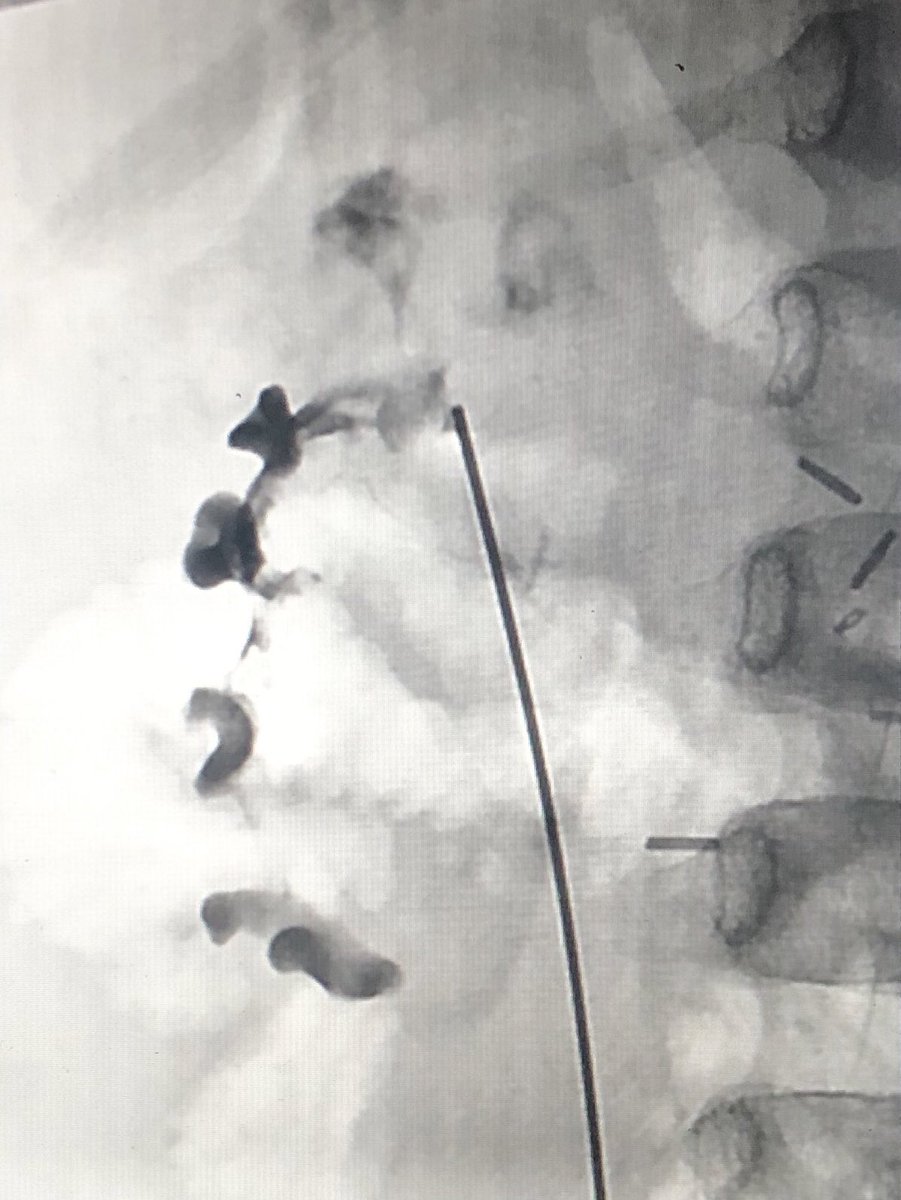

Paediatric nephrostomy

Technique

•US guidance for access to PCS

• I I  for drain catheter placement

•Seldinger technique with Micropuncture access

–Modified or single exchange

•Trocar (‘single-stick’) technique

xDistorted anatomy – calyx puncture vs pelvic puncture